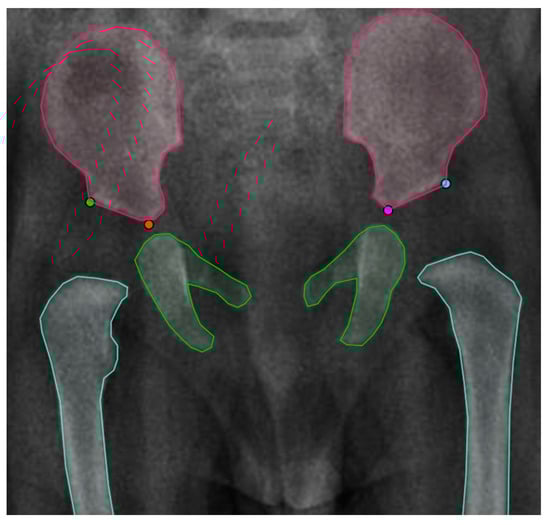

3.2.1. First Stage: Instance Segmentation

3.2.2. Second Stage: Landmark Detection